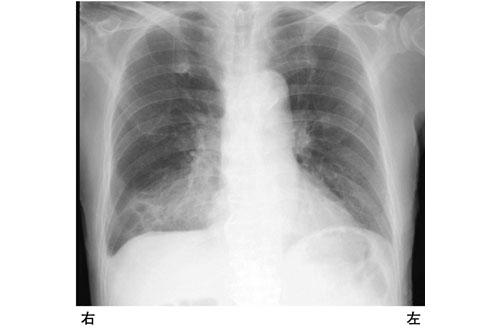

嚥下障害がある患者の胸部エックス線写真を示す。予想される理学所見はどれか。

1

胸痛

2

乾性咳嗽

3

頸静脈怒張

4

右胸部打診で鼓音

5

右胸部聴診で水疱音